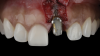

(12.) Flap reflection to assess the position of the coronal aspect of the implant and facilitate soft-tissue grafting.

Figure 12

A patient presented for the restoration of an implant that had been placed at the site of tooth No. 9, which exhibited a residual soft-tissue deficiency and an undulating facial soft-tissue morphology (Figure 11). The objective of the treatment was to change the appearance and thickness of the facial soft tissue prior to crown placement to optimize the esthetics and prevent future soft-tissue dehiscence. After flap reflection (Figure 12), a graft was acquired from the patient's tuberosity to augment the supracrestal soft tissue (Figure 13). A volume-stable collagen matrix was then placed to further increase the thickness of the soft tissue adjacent to the implant body (Figure 14), and the flap was sutured closed (Figure 15). Following a 3-month healing period, a positive change in the soft tissue's morphology was apparent; however, its volume remained deficient when compared with that of tooth No. 8 (Figure 16). When the screw-retained crown was delivered, a second graft was acquired from the tuberosity and placed to further increase the volume of the supracrestal soft tissue (Figure 17 and Figure 18). A postoperative healing period of 4 months resulted in an ideal position of the margin of tooth No. 9 with regard to its contralateral counterpart as well as more natural looking soft-tissue morphology and excellent supracrestal soft-tissue thickness (Figure 19 and Figure 20). Eight months postoperatively, the position of the gingival margin and the thickness of the soft tissue had been maintained (Figure 21 and Figure 22).